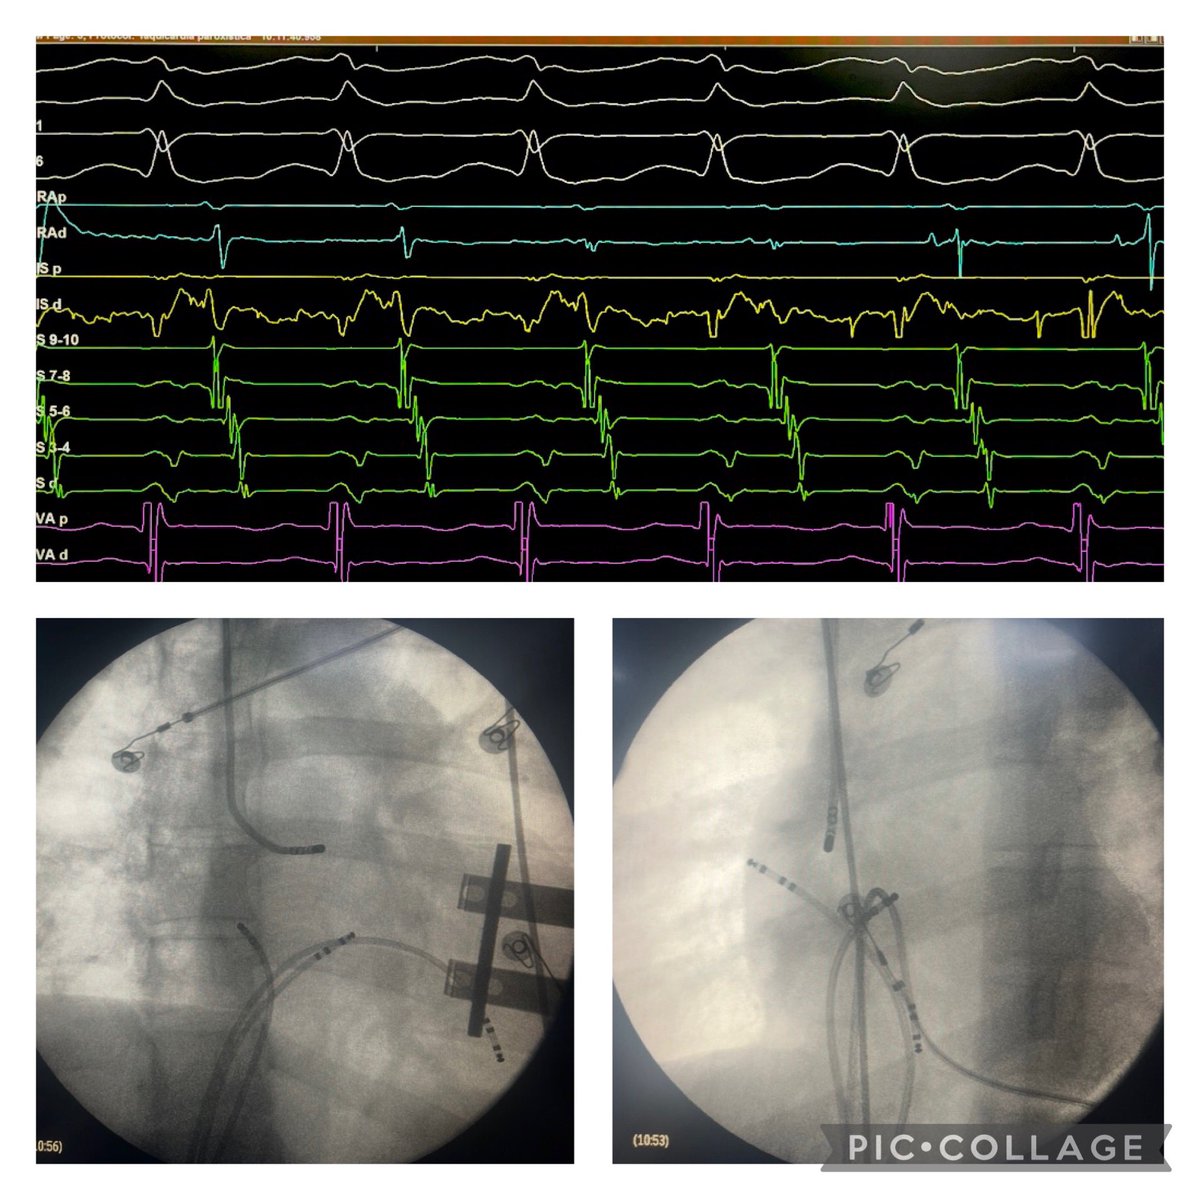

Atypical accessory pathway connection between RAA-RV. A nice tip here is to recognize what we coined “fan effect”: a remote place depolarizes HRA-HIS-CSp almost at same time in ORT Successful RFA at 3rd session. Hospital Posadas

Atypical accessory pathway connection between RAA-RV.

A nice tip here is to recognize what we  coined “fan effect”: a remote place depolarizes HRA-HIS-CSp almost at same time in ORT

Successful RFA at 3rd session.

<a href="/hospitalposadas/">Hospital Posadas</a>

Successful EGM. Look how early compared to His Channel, the earliest Atrium depolarization in the tricuspid ring. RAA base location. Ablation ON Session 3

Successful EGM.

Look how early compared to His Channel, the earliest Atrium depolarization in the tricuspid ring.

RAA base location.

Ablation ON Session 3